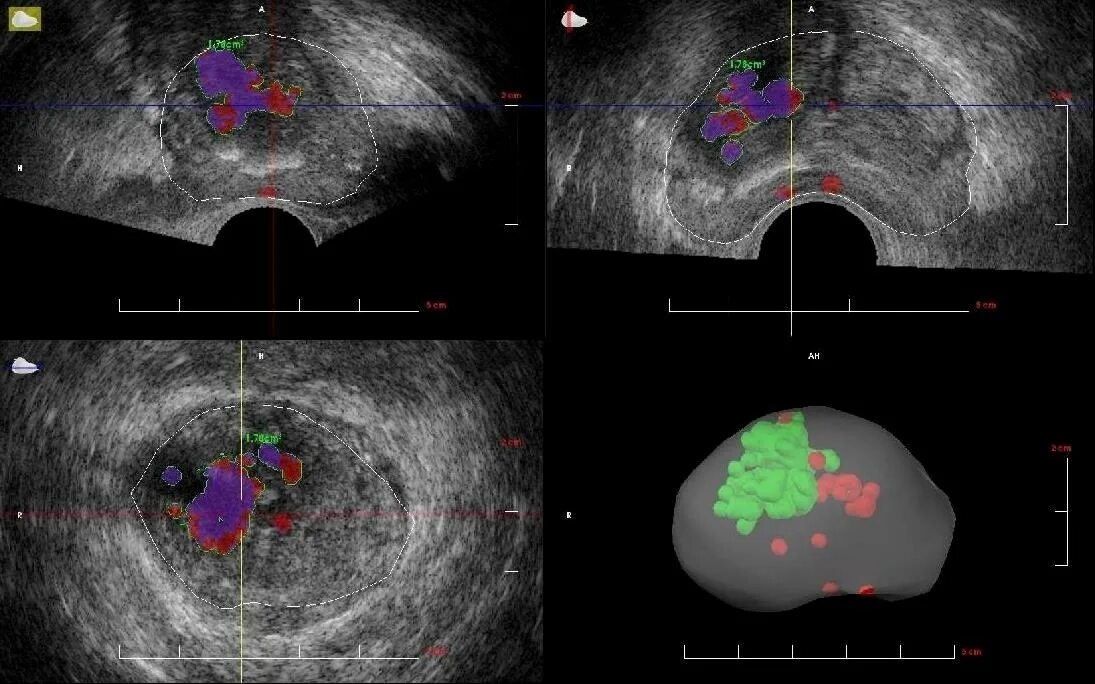

Злокачественная опухоль предстательной железы. Злокачественные новообразования простаты. Генная терапия злокачественных опухолей. Генная терапия в онкологии Карцинома предстательной железы УЗИ. Допплерография предстательной железы. Онкология предстательной железы

Карцинома предстательной железы УЗИ. Допплерография предстательной железы. Онкология предстательной железы Злокачественное новообразование предстательной железы. Карцинома предстательной железы. Susp BL предстательной железы что это. Tumor предстательной железы

Предстательная железа MRT. Мультипараметрическое мрт предстательной железы. Предстательная железа кт норма. Аденома предстательной железы мрт Гистосканнинг предстательной железы. Трансректальная биопсия предстательной железы под контролем УЗИ. Ангиография предстательной железы. Лимфоузлы в предстательной железе

Гистосканнинг предстательной железы. Трансректальная биопсия предстательной железы под контролем УЗИ. Ангиография предстательной железы. Лимфоузлы в предстательной железе Фиброз предстательной железы. Объемное образование предстательной железы. Склероз в предстательной железе

Образование предстательной железы УЗИ. УЗИ предстательной железы РПЖ. Диагностика опухолей предстательной железы

Образование предстательной железы УЗИ. УЗИ предстательной железы РПЖ. Диагностика опухолей предстательной железы Злокачественное новообразование предстательной железы. Онкозаболевания предстательной железы. Аденома простаты злокачественная. Мкб предстательной железы